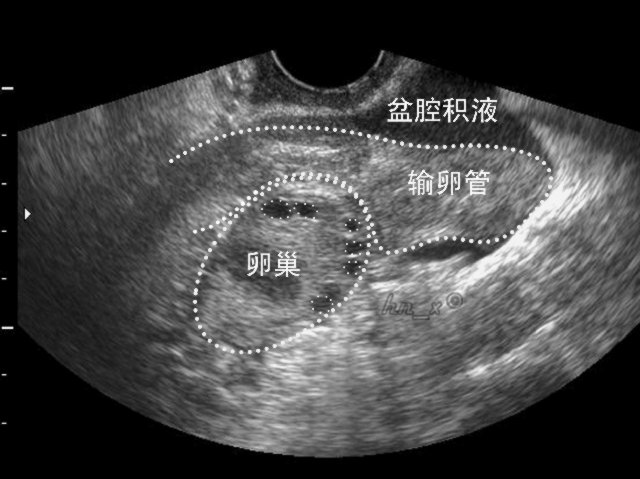

近年来,盆腔内疾病发病率升高,几乎80%的女性都会受此困扰。在临床上大多数妇女的盆腔积液是由炎症引起,是盆腔存在炎性渗出物,如果不加以治疗的话,积液会慢慢增多。

而当积液侵犯到输卵管、卵巢或其他器官时,可导致一系列妇科疾病,因此需要受到足够重视。